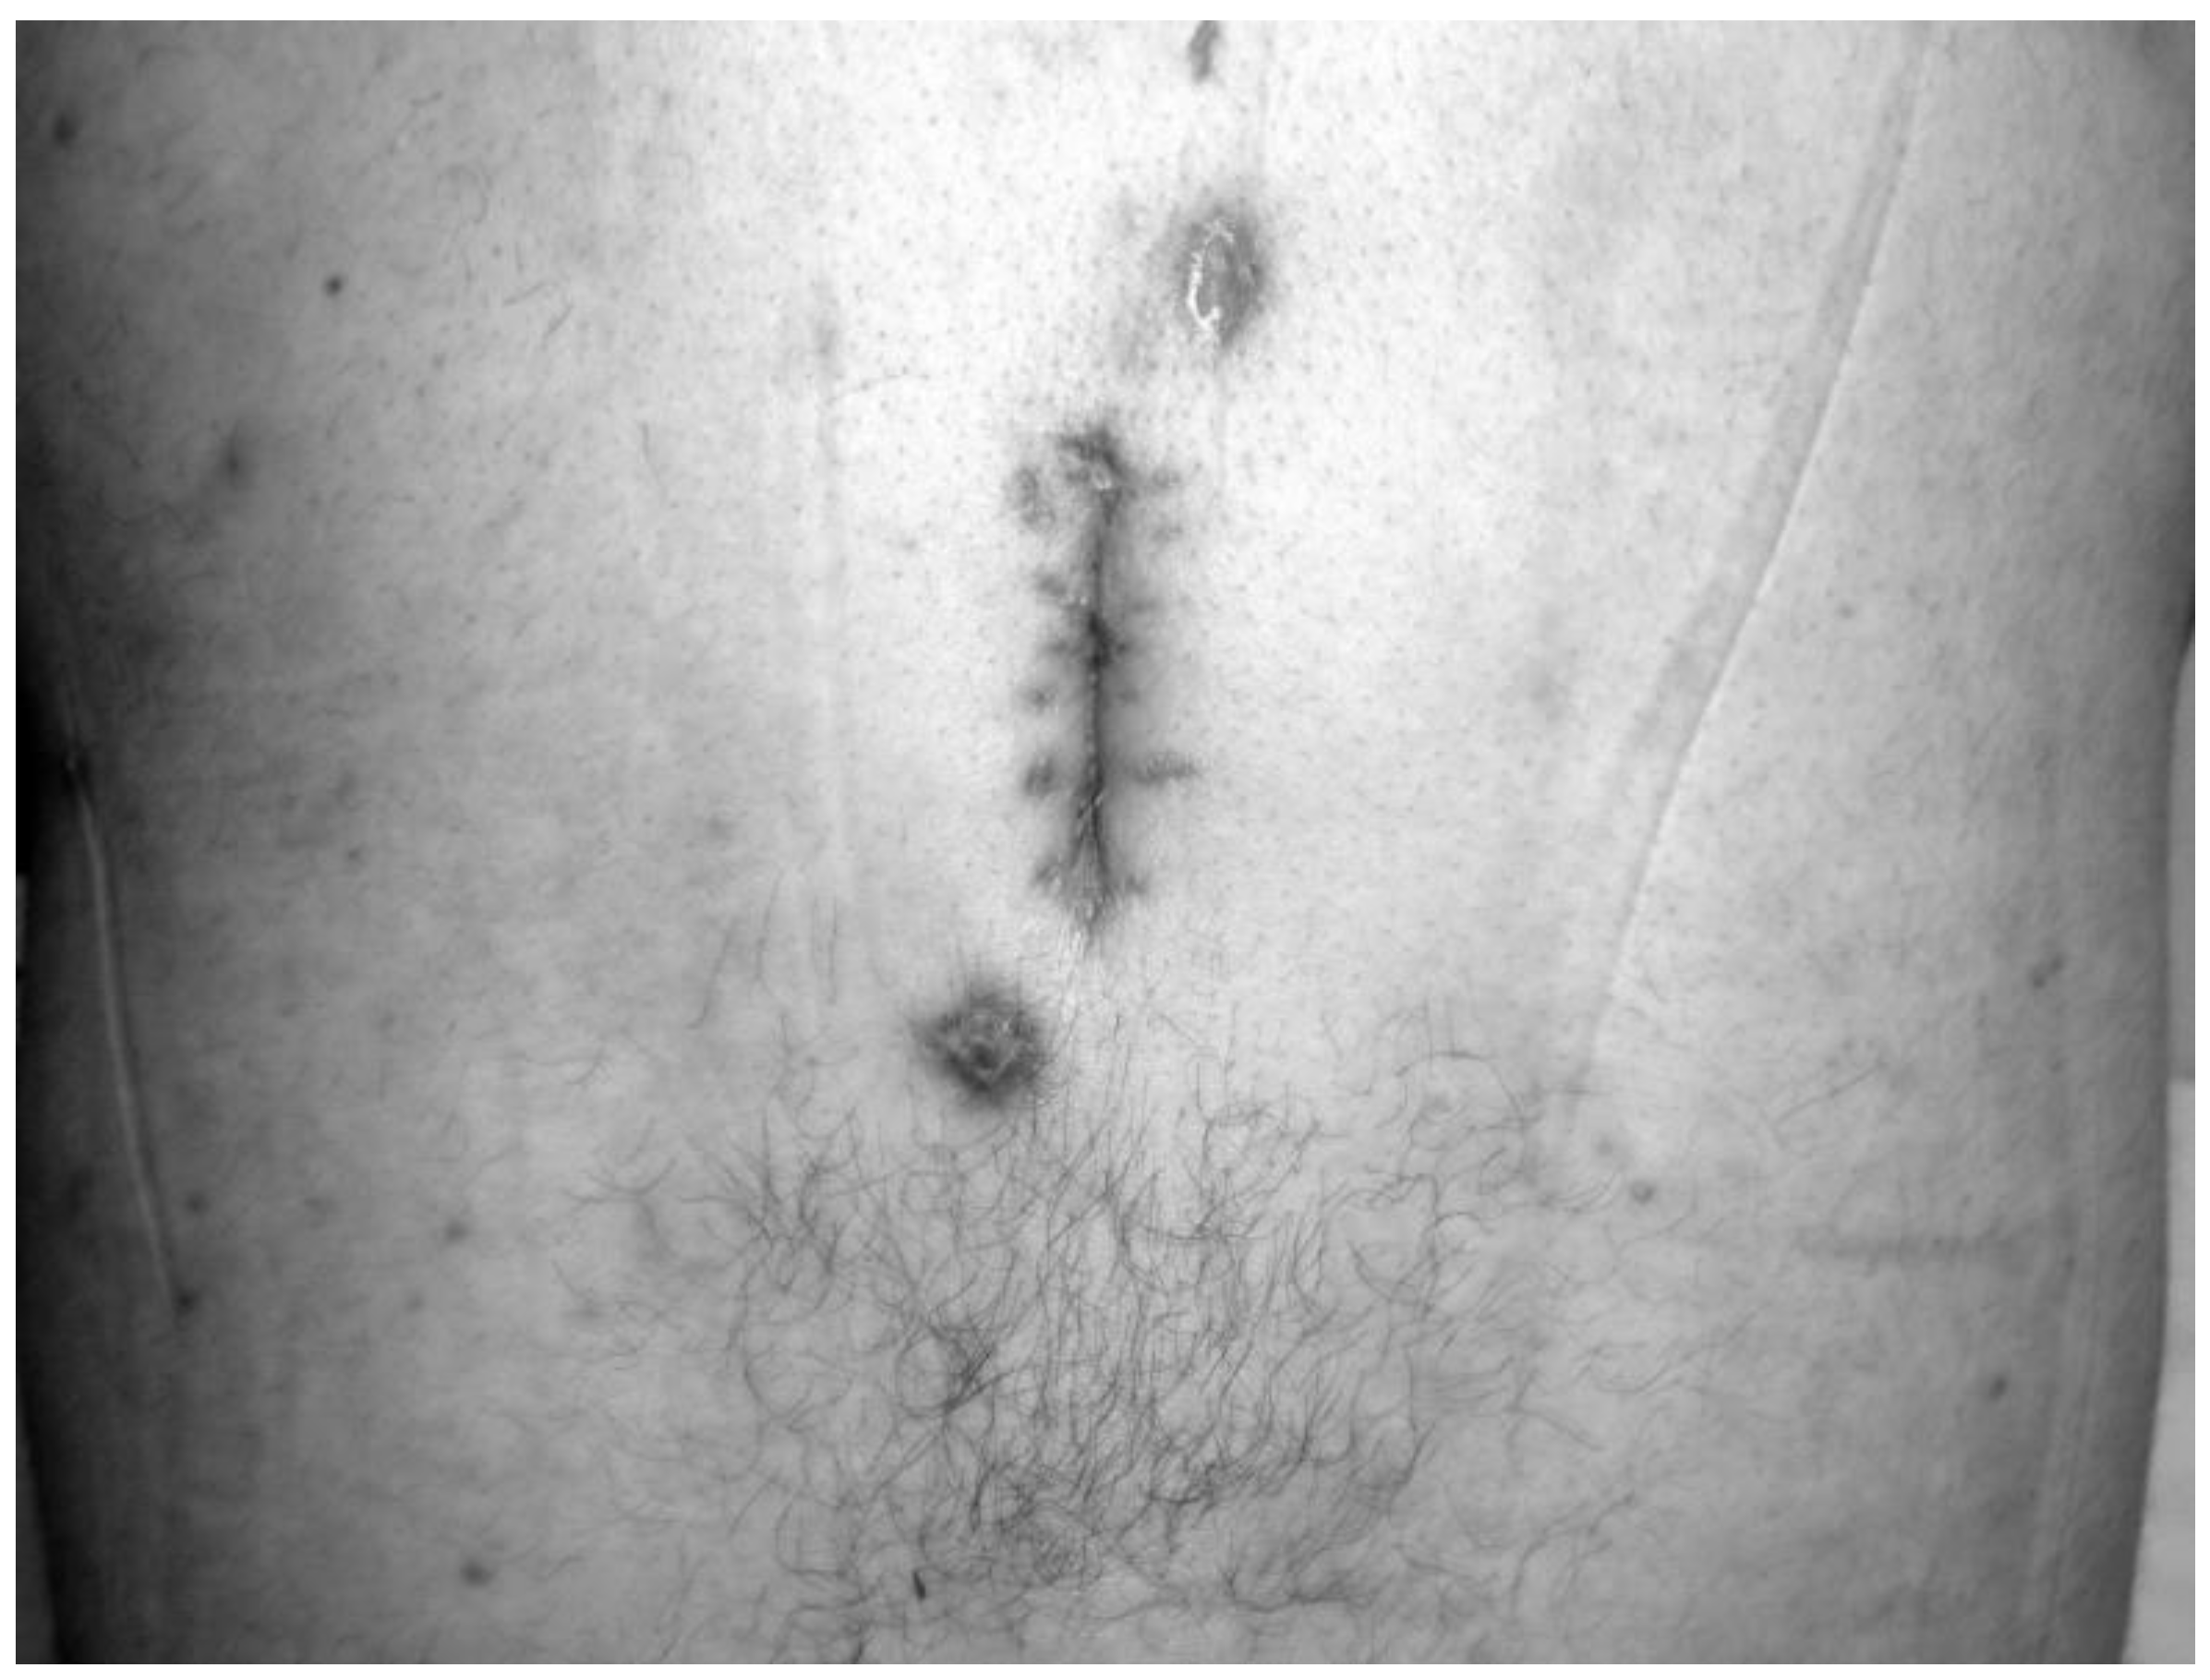

All patients who received HBO2 treatment (seven males, six females) had a prior history of spinal surgery. The primary diagnosis was spondylolisthesis in one patient, fracture in two patients, stenosis in three patients, and disc herniation in seven patients. The mean time between diagnosis and HBO2 treatment was 7.8 weeks. In patients referred after 2012, however, this time was 5.2 weeks. The primary symptom of all patients was pain. On admission, five patients (38%) were able to stand and walk without assistance, three patients (23%) were able to stand and walk with assistance, and five patients (38%) were unable to stand and walk because of severe pain. Conservative orthopedic treatment consisted of immobilization with rigid orthosis (hard cervical collar, thoracolumbar rigid brace, lumbosacral corset), which continued until complete healing of infection. There was also a discharging wound or sinus in the operation site in five patients. A daily wound dressing was applied in this group. In four of these five patients (80%), complete wound healing was achieved at the end of HBO2 therapy (Figure 1 and Figure 2).

Figure 1. The appearance of the wound with purulent drainage in the operation site prior to HBO2 treatment.

Figure 2. Discharge from the wound site stopped and complete wound healing was achieved at the end of HBO2.